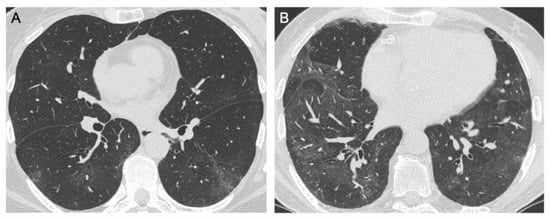

3.1.1. Ground Glass Opacities

3.1.2. Consolidations